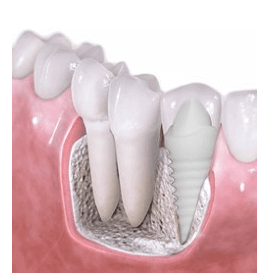

Dr. Rajaski and Dr. Adams are long time friends from the University of Maryland Dental School going all the way back to 1997. Dr. Rajaski has practiced in private practice and at the University of Maryland Dental School as a part time faculty member. Maryland Holistic Dentist is happy Dr. Rajaski as one of our full time providers. Dr. Rajaski is a member of the IAOMT (International Academy of Oral Medicine and Toxicity) and is board certified as a dentist and a dental sedation professional. Dr. Rajaski is a holistic-minded doctor and combines a variety of biological and conventional techniques into his practice. Dr. Raski recognizes that the oral cavity is central to overall health. He implements many holistic techniques to his treatments such as platelet rich fibric (Dental PRF), ozone and non-metal zirconia implants.